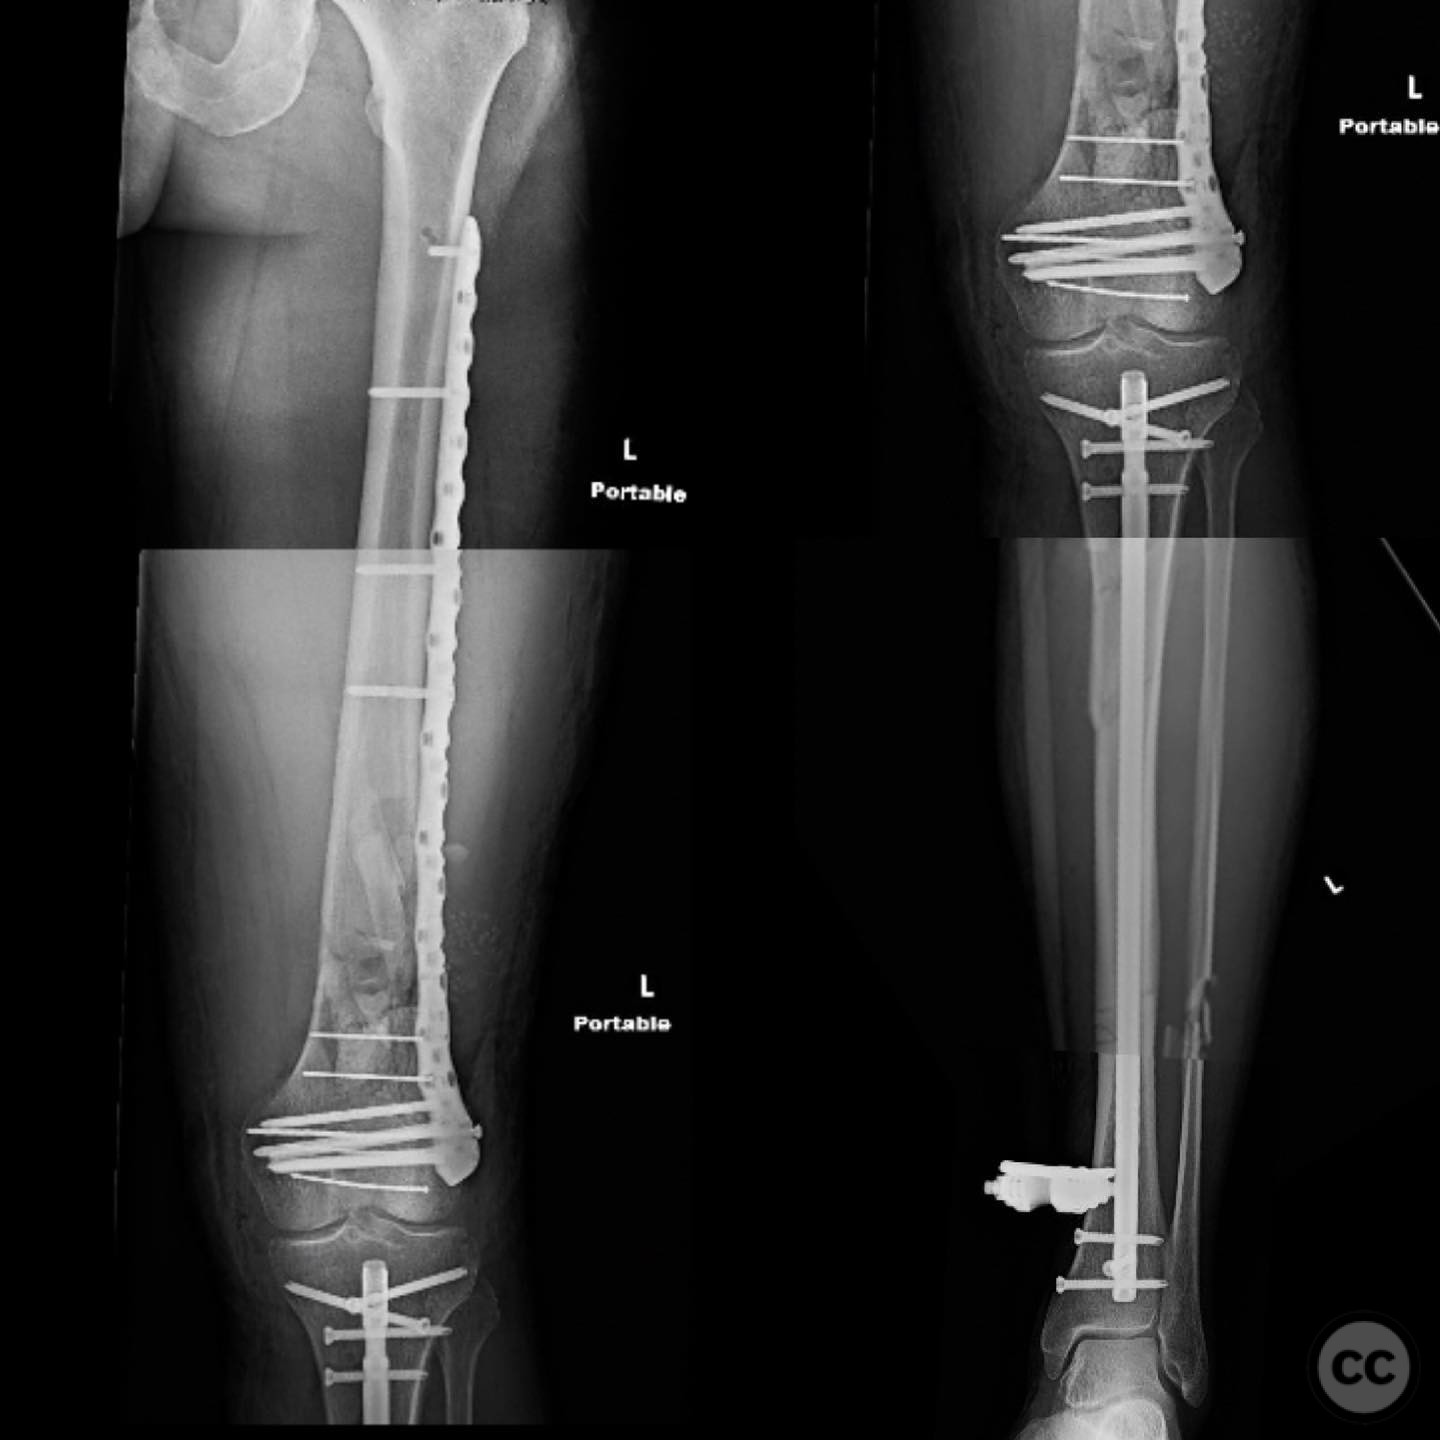

Clinical and radiological findings:  A 44-year-old male cyclist was involved in a collision with a car, resulting in open fractures of the distal femur and segmental tibia. The femoral fracture presented with a 4 cm transverse wound on the anterior aspect, while the tibial fracture had a 2 cm anterolateral wound at the distal site. There were no associated head, chest, or abdominal injuries, and compartment syndrome was not present. Vascular examination was unremarkable.

Planning remarks:  The preoperative plan involved initial debridement and irrigation of both open fractures. The tibia was prioritized for intramedullary nailing, followed by spanning external fixation of the distal femur. Definitive fixation of the distal femur was planned for two days post-initial stabilization.

Anatomical surgical approach:  For the tibia, a longitudinal incision was made to access the proximal tibial start site for intramedullary nailing. Percutaneous clamps were utilized for reduction, supplemented by blocking screws as needed. For the distal femur, an external fixator was applied initially, followed by an in situ lateral approach for plating after reduction was achieved.

The tibial nailing required precise identification of the start site under fluoroscopic guidance, with percutaneous clamps aiding in reduction. Blocking screws were considered but not necessary due to successful reduction with clamps alone. The distal femur presented challenges in achieving coronal and sagittal alignment, necessitating reliance on the external fixator for reduction before proceeding with plating.

Postoperative protocol:   Postoperative rehabilitation included early mobilization with weight-bearing as tolerated on the tibia, while the femur required protection until definitive fixation was achieved. Progressive weight-bearing was introduced following femoral plating.

Orthopaedic implants used:   Intramedullary nail for tibia, external fixator for initial femoral stabilization, and locking plate for definitive femoral fixation.